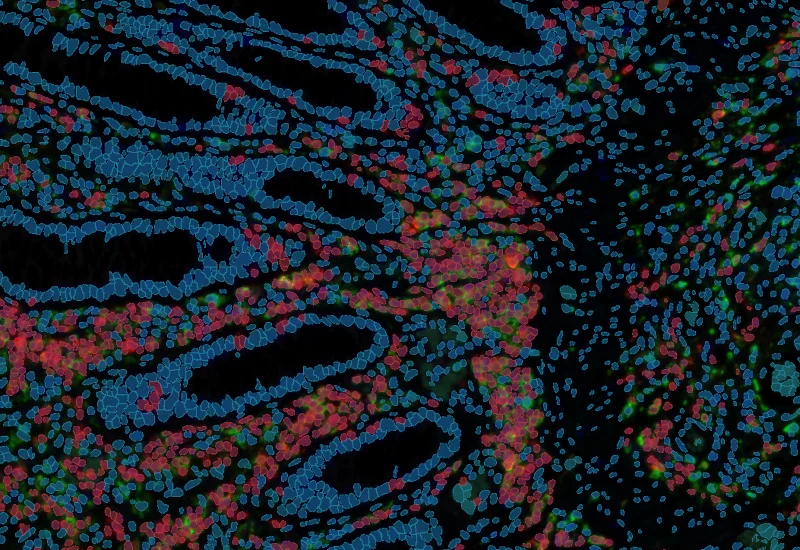

The IF 2 App provides single cell-based co-expression analysis for two IF markers. It segments cells into their nucleus, perinuclear area, and/or cytoplasm. Each segmented cell compartment is measured for up to 20 intensity, statistic, and morphometric parameters that can be displayed in and exported into scattergrams and histograms.

App Category 1

The IF 3 App provides single cell-based co-expression analysis for three IF markers. It segments cells into their nucleus, perinuclear area, and/or cytoplasm. Each segmented cell compartment is measured for up to 20 intensity, statistic, and morphometric parameters that can be displayed in and exported into scattergrams and histograms.

The IF 4 App provides single cell-based co-expression analysis for four IF markers. It segments cells into their nucleus, perinuclear area, and/or cytoplasm. Each segmented cell compartment is measured for up to 20 intensity, statistic, and morphometric parameters that can be displayed in and exported into scattergrams and histograms.

The IF Hi-Plex 50 App combines and analyses images of the same IF-stained tissue section, acquired up to 50 times with different markers. The App enables the detection of the cellular phenotypes of specific IF-stained cell populations. It segments cells into their nucleus, perinuclear area, and/or cytoplasm. Each segmented cell compartment is measured for up to 20 intensity, statistic, and morphometric parameters that can be displayed in and exported into scattergrams and histograms.

The IF Immune Status in Situ App provides a phenotypic characterization of immune cells in reference to detected metastructures (e.g., tumors, glands) and measures the distance of detected cellular objects to the metastructure boundary (within and/or outside). Distance ranges are also definable. Each segmented cell compartment is measured for up to 20 intensity, statistic, and morphometric parameters, as well as the distance of each cell to the areas boundary.

The IF Cellular Microenvironment App allows to determine the cellular phenotype of specific IF-stained cell populations and establishes their spatial relationship between each other and their neighboring cells/cell populations, including those with metastructures (e.g., blood vessels, tumors) in their vicinity. It is especially suited for proximity and infiltration analyses.

The IF Cellular Contact App allows for the determination of the cellular phenotype of specific IF-stained cell populations and establishes the cellular contacts to their neighboring cells (the number of markers is technically unlimited). If needed, the App provides a separation of nuclei in tissues with high cellular densities. The App outputs parameters such as staining intensity per marker and morphometric parameters for each segmented cell/cell compartment, as well as the number and percentage of cells of different phenotypes in direct contact.

Images: courtesy of Naoki Kaneko/Shiv Pillai (PI), Ragon Institute of MGH, MIT and Harvard, Boston, MA USA.